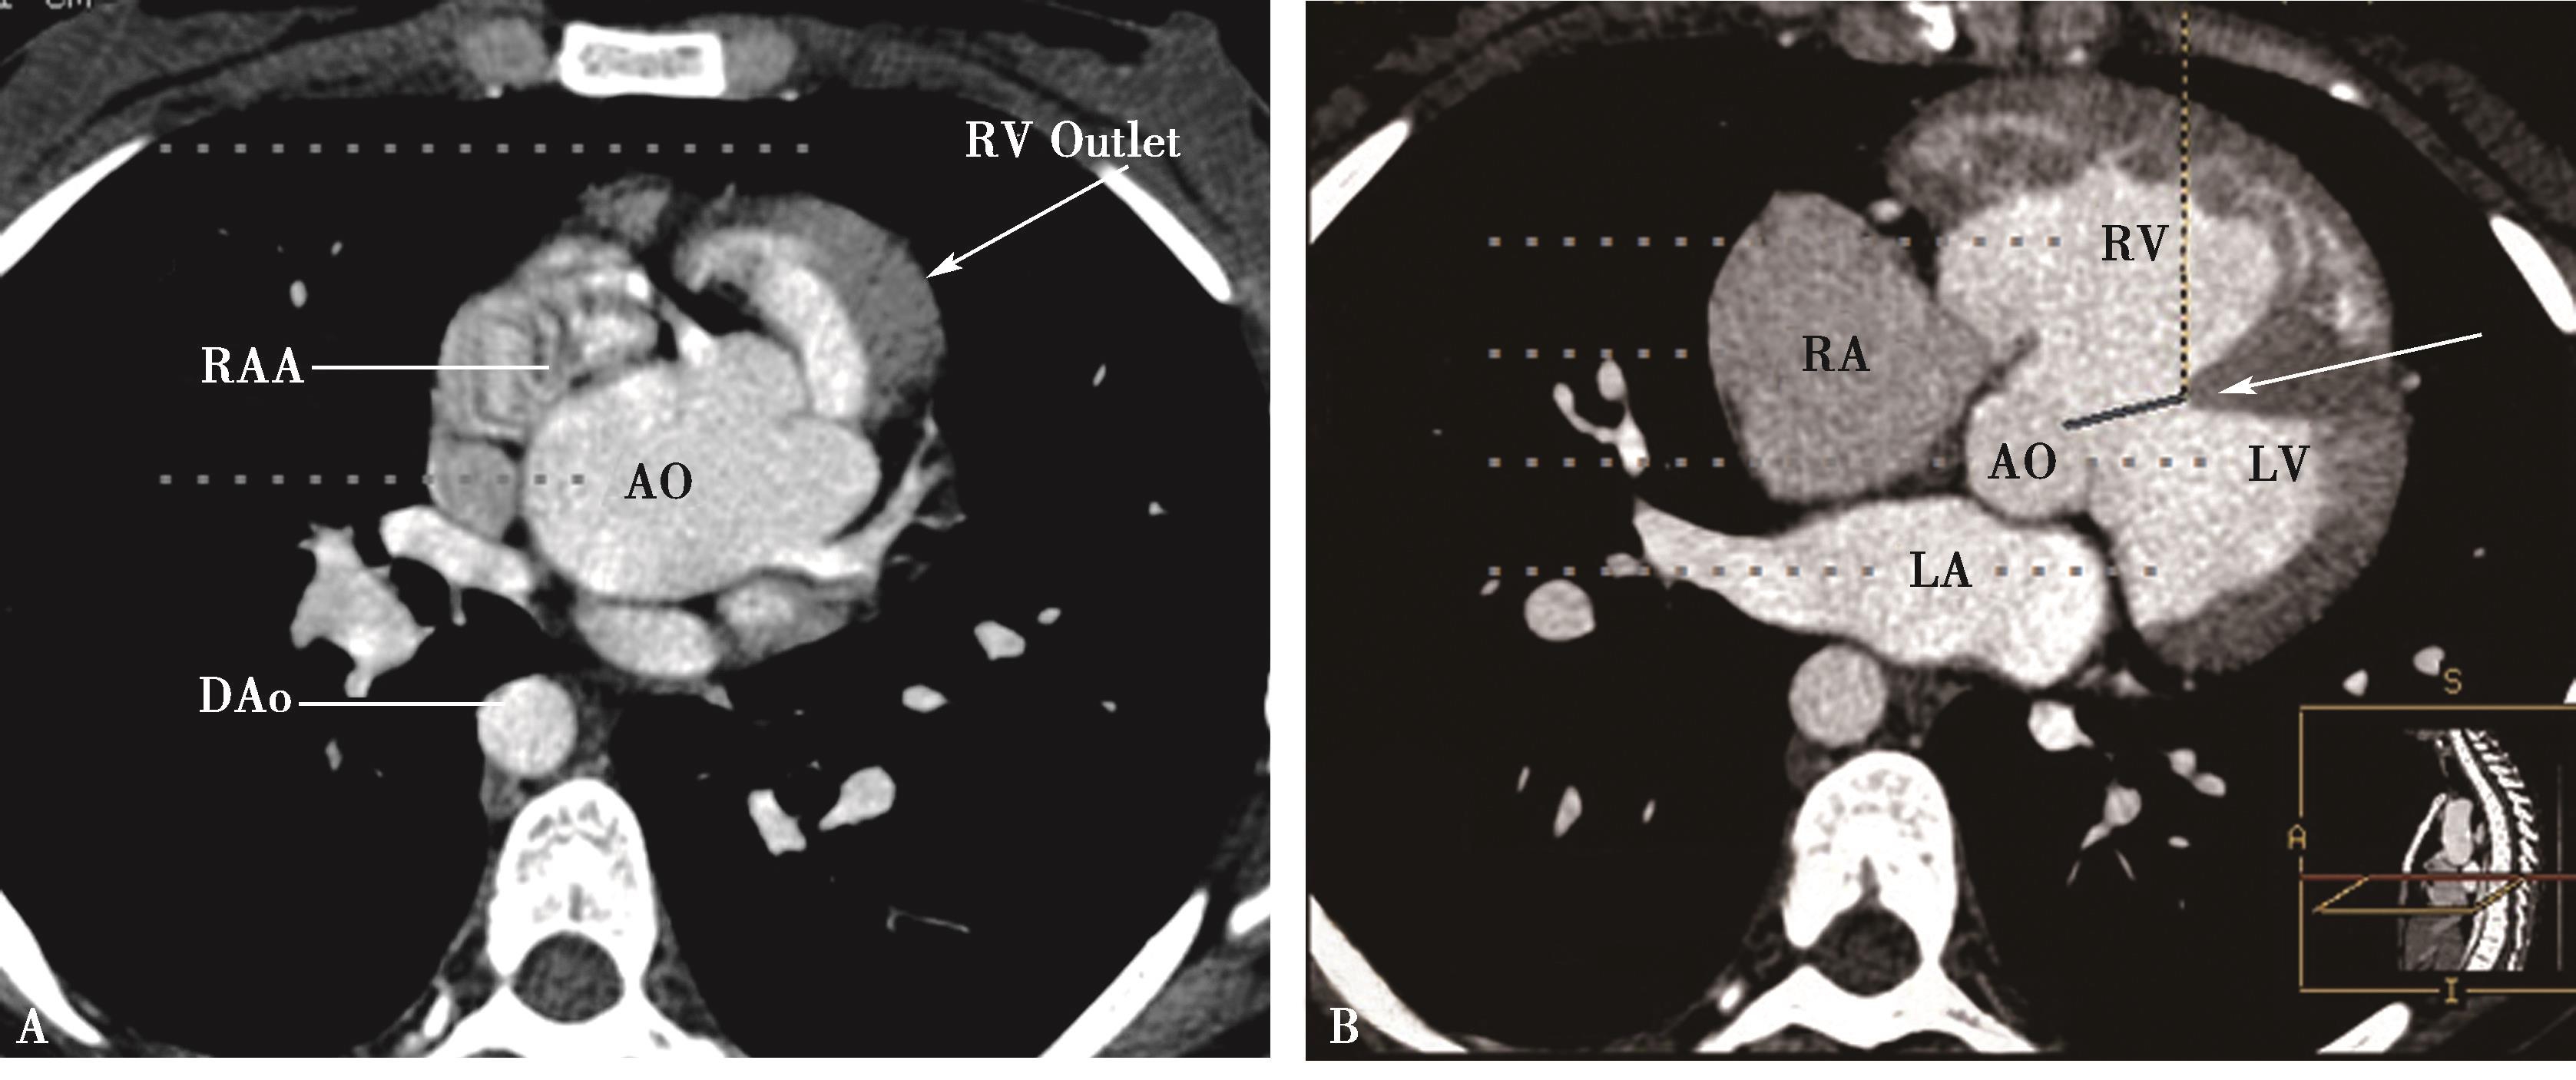

横断扫描是诊断检查基础(图8-5-2, 图8-5-3)。

图8-5-2 “肺动脉”型大动脉炎

AB.CT横断图像,右肺动脉闭塞(A↑),左锁骨下动脉闭塞、钙化(B↑);C.肺动脉造影,右肺动脉闭塞(↑);D.主动脉造影,左锁骨下动脉闭塞(↑)。诊断:“肺动脉”型大动脉炎。证实CT所见

1)管壁特点:

大动脉炎以累及主动脉及其主要分支为主。约50% ~80%累及肺动脉主干,叶-段分支。可以独立发生于肺动脉者,但少见。①活动期(早期):受累血管管壁明显增厚;不引起管腔狭窄。②慢性期:管壁逐渐变为向心性不规则增厚,引起管腔狭窄闭塞;管壁出现钙化;随年龄增长,有动脉硬化性斑块形成,管壁不规则改变加剧。

2)管腔特点:

①管腔无变化:早期(活动期)虽然管壁增厚,但是管腔可以无变化。②管腔狭窄-闭塞:随着疾病进展,管壁向心性不规则增厚加重,管腔狭窄-闭塞。③动脉瘤形成:部分可见管腔不规则瘤样扩张,或动脉瘤形成,可呈“串珠样”改变;可发生附壁血栓。少见假性动脉瘤形成。

图8-5-3 “肺动脉”型大动脉炎

A.CT横断图像,右肺动脉闭塞(▲),左肺动脉及分支多发狭窄-闭塞(↑);B.横断图像,左颈总动脉、左锁骨下动脉开口部管壁增厚(晕环征),管腔狭窄不明显(↑);C.肺动脉造影,右肺动脉闭塞(△),左肺动脉及分支多发狭窄(↑);D.主动脉造影,左颈总动脉、左锁骨下动脉开口部管壁僵硬,未见明显狭窄(↑)。CT诊断:“肺动脉”型大动脉炎

3)累及范围:

累及肺动脉主干-叶-段以上大中血管,右侧多于左侧,右肺上叶动脉最易受侵犯。约占50%~70%。

4)主动脉及其重要分支病变:

大动脉炎主要是累及体动脉为主,因此一定要相应注意观察,并做出诊断,对肺动脉病变定性有重要价值。

5)心脏改变:

注意观察有否房室增大。如果以累及肺动脉为主,常有肺动脉高压发生,注意有否存在右心室肥厚、扩大,右心房扩大。